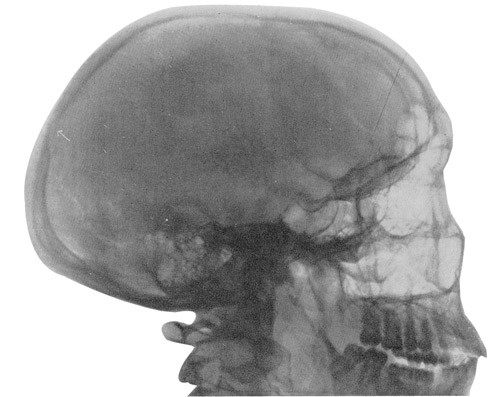

Røntgen – doktor Bohne, Trondheim – 23. april: I bakhodet sees en lett dislokasjon av kraniebenet – fractura cranii. X-foto vedlegges.